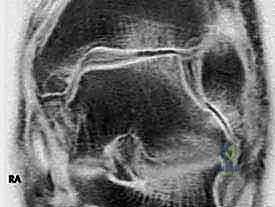

3. التصوير بالرنين المغناطيسي (MRI)

يُعد الرنين المغناطيسي المعيار الذهبي لتقييم الأنسجة الرخوة. يسمح للدكتور هطيف برؤية مدى تمزق رباط الدالية (جزئي أم كلي)، وتقييم حالة وتر الظنبوب الخلفي، واكتشاف أي إصابات مصاحبة في الغضاريف المفصلية (Osteochondral Lesions) التي قد تتطلب تدخلاً بالمنظار.